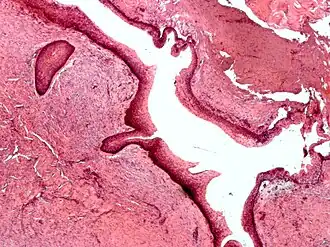

Histologicamente, o QO é caracterizado como uma cavidade cística revestida por uma camada fina de epitélio estratificado escamoso paraqueratinizado, com uma camada basal de células cuboidais ou colunares hipercromáticas em paliçada.[4][5] A queratina na superfície possui um aspecto corrugado característico.[4]

Histologia com ampliação intermediária de um ceratocisto odontogênico.